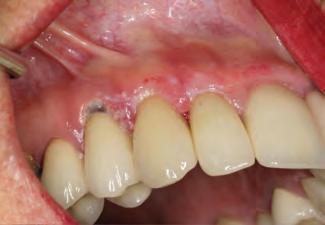

A 31-year-old woman presented with cosmetic concerns regarding her smile and requested a conservative enhancement. After clinical and radiographic analysis, digital 35mm photographs were taken and reviewed by the restorative clinician, technician, and surgeon (Fig 1). A digital impression was taken of the maxillary and mandibular arches using an intraoral scanner (Trios 3, 3Shape; Fig 2), and a smile design was developed with NemoSmile Design 3D software (Nemotec; Fig 3a). This allows for a facially driven smile frame to be created using reference lines of facial and smile proportions and natural teeth shapes and textures from the digital library (Fig 3b).

After developing the simulated mock-up, a 3D-printed resin model was created using CAD software (Fig 4a), and a clear PVS matrix (Exaclear, GC America) was fabricated to replicate the printed diagnostic wax-up using a nonperforated tray (Fig

Fig 1 Preoperative clinical views of a 31-year-old woman presenting with diastemas and limited tooth visibility. (top) Portrait. (center row) Intraoral views. (bottom row) Smile.

4b). This matrix was used to create an intraoral motivational mock-up with bis-acryl composite (Luxatemp Ultra, DMG). This additive mock-up provides the interdisciplinary team with an intraoral translation for evaluation (Fig 5). Upon evaluation of the digital smile frame and the clinical translation, it was determined that multiple esthetic and restorative requirements were necessary for an optimal biologic framework, and the interdisciplinary team determined the best sequence for these procedures. The patient was presented with the interdisciplinary treatment possibilities that included restoring the maxillary anterior teeth and premolars with a minimally

invasive preparationless procedure or with less conservative veneer preparations. The restorative materials discussed included injectable resin composites and ceramic (ie, feldspathic, pressable, machinable). For an optimal biologic framework and health, it was determined that connective tissue grafting would be necessary for treatment of the recessiontype defects on the maxillary left central and lateral incisors, canine, and premolars. The patient opted for the conservative preparationless composite veneers using the injectable resin technique followed by a connective tissue surgical procedure using the tunneling technique.